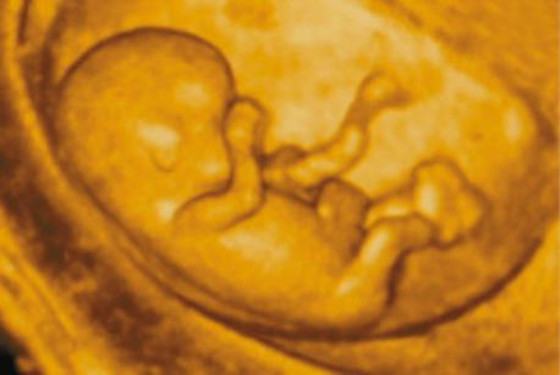

随着人们现代生活的进步与改善,虽然对生男生女已经不会再那么在意,但是对于少部分追求生儿子的家庭来讲,还是有些渴望的。怀孕三个月男孩的征兆表现有哪些,来听听医生是如何说的吧。

怀孕三个月男孩的征兆